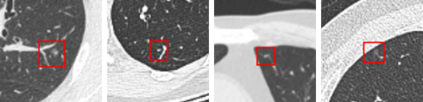

Convolutional neural networks (CNNs) have been demonstrated to be highly effective in the field of pulmonary nodule detection. However, existing CNN based pulmonary nodule detection methods lack the ability to capture long-range dependencies, which is vital for global information extraction. In computer vision tasks, non-local operations have been widely utilized, but the computational cost could be very high for 3D computed tomography (CT) images. To address this issue, we propose a long short slice-aware network (LSSANet) for the detection of pulmonary nodules. In particular, we develop a new non-local mechanism termed long short slice grouping (LSSG), which splits the compact non-local embeddings into a short-distance slice grouped one and a long-distance slice grouped counterpart. This not only reduces the computational burden, but also keeps long-range dependencies among any elements across slices and in the whole feature map. The proposed LSSG is easy-to-use and can be plugged into many pulmonary nodule detection networks. To verify the performance of LSSANet, we compare with several recently proposed and competitive detection approaches based on 2D/3D CNN. Promising evaluation results on the large-scale PN9 dataset demonstrate the effectiveness of our method. Code is at https://github.com/Ruixxxx/LSSANet.